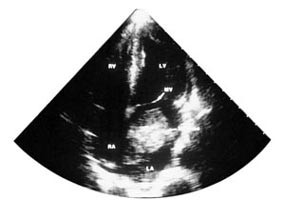

Transtorakal ekkokardiografi er avgjørende for diagnosen av tumor cordis (fig 3). Det kan være nødvendig med supplerende transøsofageal ultralydundersøkelse i den preoperative evalueringen for nøyaktig å lokalisere tumors utbredelse. Computertomografi og magnetisk resonanstomografi som ledd i utredningen er indisert hvor man ønsker ytterligere informasjon om tumorutbredelse og tumorinfiltrasjon ved mistanke om malignitet. Hos pasienter over 40 år har vi valgt å utføre preoperativ, selektiv koronarangiografi med tanke på ev. behandlingstrengende koronarsykdom. Angiografi kan også påvise patologiske karmønstre.